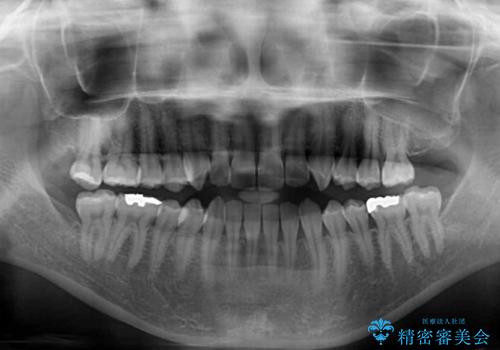

- 上下前歯の叢生と奥歯の反対咬合を気にして来院された患者様です。

インビザラインを用い、下顎はIPR(歯と歯の間を削る)と歯列全体を後方に移動させ、上顎は側方に拡大させることで歯列を改善していくこととしました。

骨格的に下顎が左側前方にずれているため、上下正中のズレや左右奥歯の咬み合わせを理想的な状態とすることは困難でした。